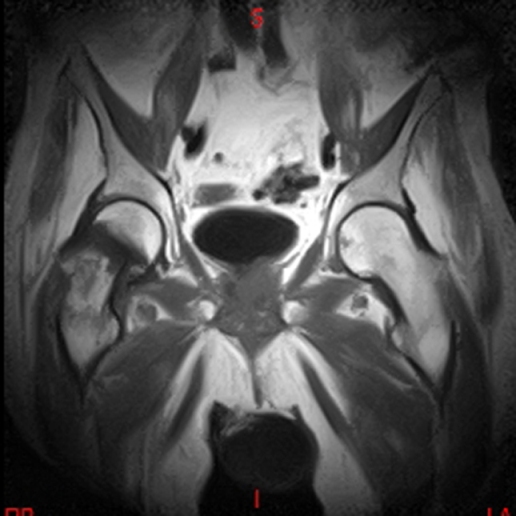

• RESONANCIA NORMAL SACROILIACAS COR T2

• RESONANCIA NORMAL CAIS T2 CORONAL

• RESONANCIA NORMAL CAIS T2 AXIAL